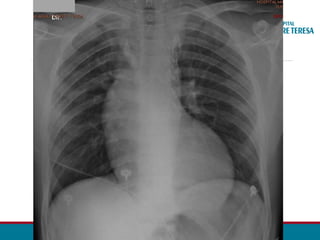

[...]

• Dilatação das artérias torácicas internas podem ser vistas

no perfil como densidade de partes moles.

• Aumento do Ventrículo Esquerdo

• Ápice cardíaco se projeta inferiormente e lateralmente à E

• Abaulamento margem cardíaca

• Sinal de Hoffman Rigler positivo

RADIOGRAFIA TORÁCICA

• Dilatação das artérias mamárias internas podem ser vistas

Sinal de Hoffman – Rigler ( > VE)

Extensão da borda posterior ventricular  1,8 cm

posteriormente à borda da Veia cava.

(medido à 2cm acima da intersecção VCI x borda ventricular)